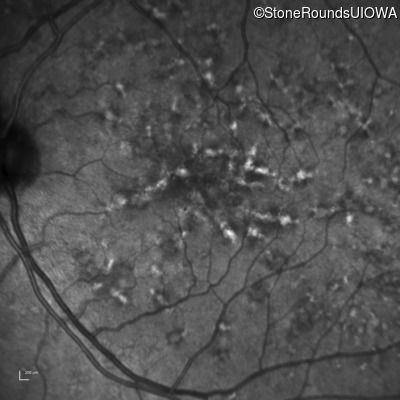

Age at visit: 49 years

Age at visit: 49 years (Visit 2)